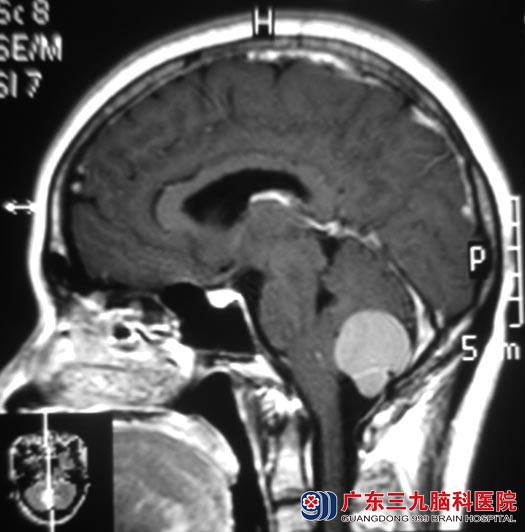

三天前在上班时,突发头痛、头晕,症状明显加重,在同事和领导的一再督促下,张小姐终于去当地医院检查,头颅MR提示:小脑蚓部占位,大小约2.5cm×2.0cm×2.0cm,考虑蛛网膜囊肿伴出血或表皮样囊肿。

▲手术前